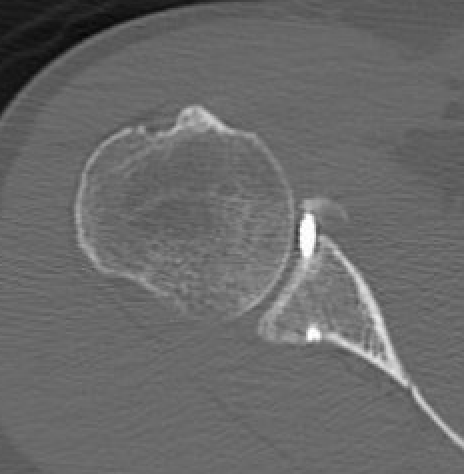

Bone block positioning

Concepts

- coracoid must not overhang medial to avoid osteoarthritis

- coracoid < 5 mm medial to glenoid rim

- coracoid lower half of glenoid 2 - 5 o'clock

- fixation screws purchases posterior glenoid cortex

- screws do not penetrate articular surface

Graft malposition

Screws and graft too medial

Bone graft too medial

Coracoid graft too superior on glenoid